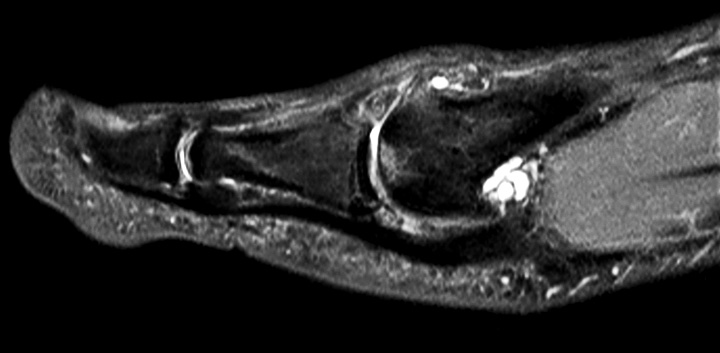

Axial PDw mDIXON TSE  (water only)

-